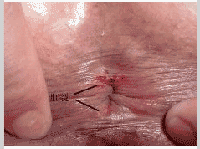

肛裂长期反复感染,病情会越来越重,形成“肛裂五联症”——肛管溃疡、肛乳头肥大、哨兵痔、肛窦炎和肛瘘。

1、溃疡形成期:创口有不良肉芽增生。创底见有环状纤维,创缘皮肤增生。

2、慢性溃疡期:创口陈旧性溃疡,刨底可见内括约肌。

3、慢性溃疡并发其他:合并肛乳头炎、肛窦炎、梭形溃疡、肛门梳硬结、潜性瘘管等病变。